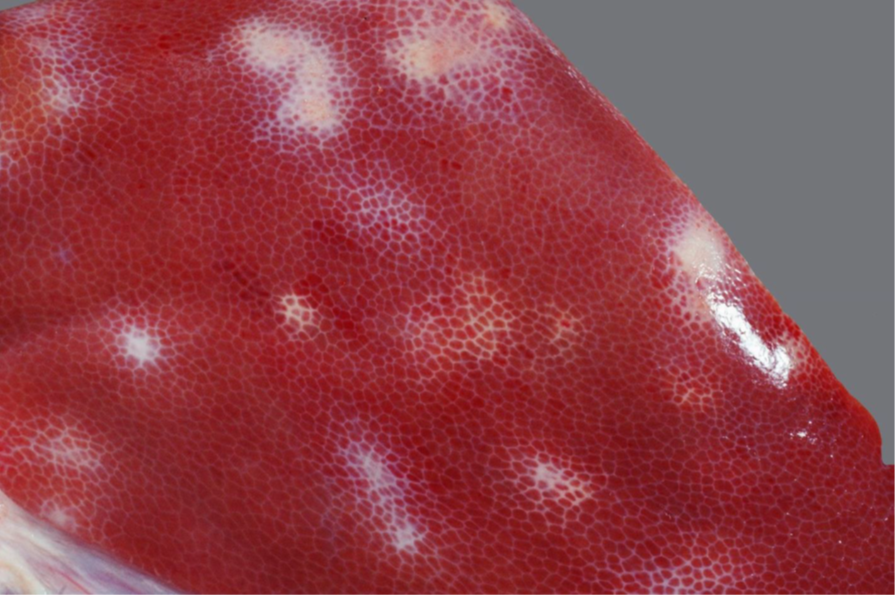

Schwein, Niere: Hochgradige, akute, diffuse Glomerulonephritis

Niere

• Helle,geschwollene Nieren mit teigiger Konsistenz

• Parenchym von zahlreichen punktförmigen roten Herden durchsetzt

Hochgradige, akute, diffuse Glomerulonephritis

Glomerulonephritis = Entzündung im Bereich der Glomerula und des umgebenden Interstitiums einschließlich der

Gefäße

Pathogenese: Immunpathologische Vorgänge spielen die überragende Rolle!

• Ablagerung von zirkulierenden Immunkomplexen (Antigen-Antikörper-Komplexe) oder

• Bildung von Antikörpern gegen Antigene der glomerulären Basalmembran

→ Komplementaktivierung → neutrophil-granulozytäre Infiltration und damit einhergehende Schädigung

(Fibrinexsudation, Nekrose, Schwellung und Proliferation von Endothel-, Epithel- und Mesangiumzellen,

Vermehrung der mesangialen Matrix sowie Verdickung und Auffaserung der Basalmembran)

Folgen: → primär Filtrationsstörungen (Proteinurie, Hämaturie, Oligurie/Anurie)

→ sekundär Beeinträchtigung tubulärer Funktionen

→ Retention harnpflichtiger Substanzen (Azotämie/Urämie)

Häufige Ursachen einer Immunkomplex-Glomerulonephritis:

Schwein – Porzines Dermatitis Nephropathie-Syndrom (PDNS)

Rind – Bovine Virusdiarrhoe (BVD)

Pferd – Equine infektiöse Anämie (EIA)

Hund – Leishmaniose, systemischer Lupus erythematodes, Dirofilariose, HCC, Pyometra

Katze - FeLV-Infektionen, FIP

DDx: petechiale Blutungen z.B. Europäische/Afrikanische Schweinepest (anzeigepflichtig)